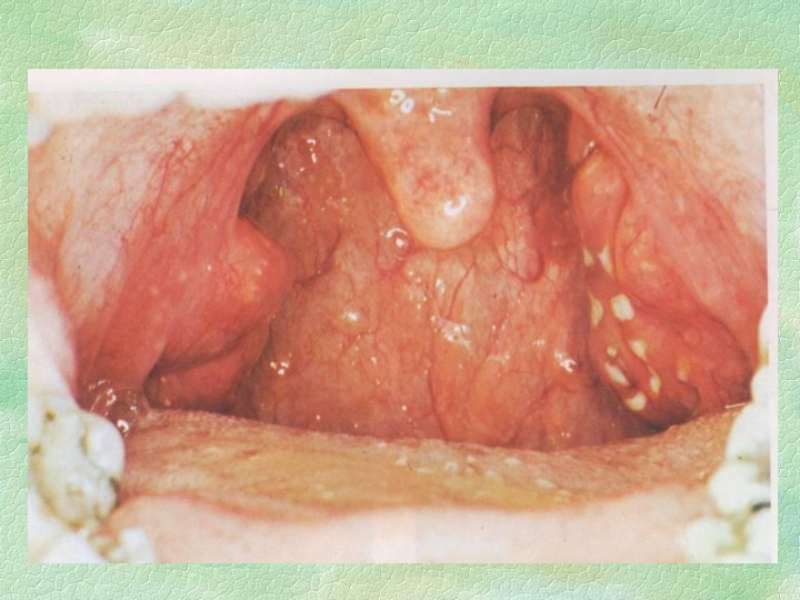

Слайд 35Орофарингоскопія

Мигдалики значно збільшені, почервонілі та різко болючі при дотику

шпателем.

Крізь їх пурпурово-червону слизову оболонку просвічується велика кількість круглих,

завбільшки 1-3 мм, жовтуватих або жовтувато-білих гноячків, що злегка підвищуються над поверхнею мигдаликів (ніби “зоряне небо”). Цими гноячками є нагноєні фолікули мигдаликів.